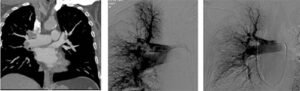

Con approccio dalla vena giugulare interna (collo) o dalla vena femorale comune (inguine),

il Radiologo Interventista porta un catetere dedicato nella sede del trombo in arteria

polmonare. La corretta posizione viene controllata con le radiazioni e mezzo di contrasto.Per i Radiologi Interventisti, le possibilità sono molteplici:

➜ Trombolisi catetere-diretta: iniezione loco-regionale di farmaco fibrinolitico

(che non poteva essere somministrato per via sistemica)➜ Trombectomia meccanica:

- Frammentazione del trombo

- Aspirazione del trombo

- Trombectomia reolitica

- Trattamenti di trombectomia combinati